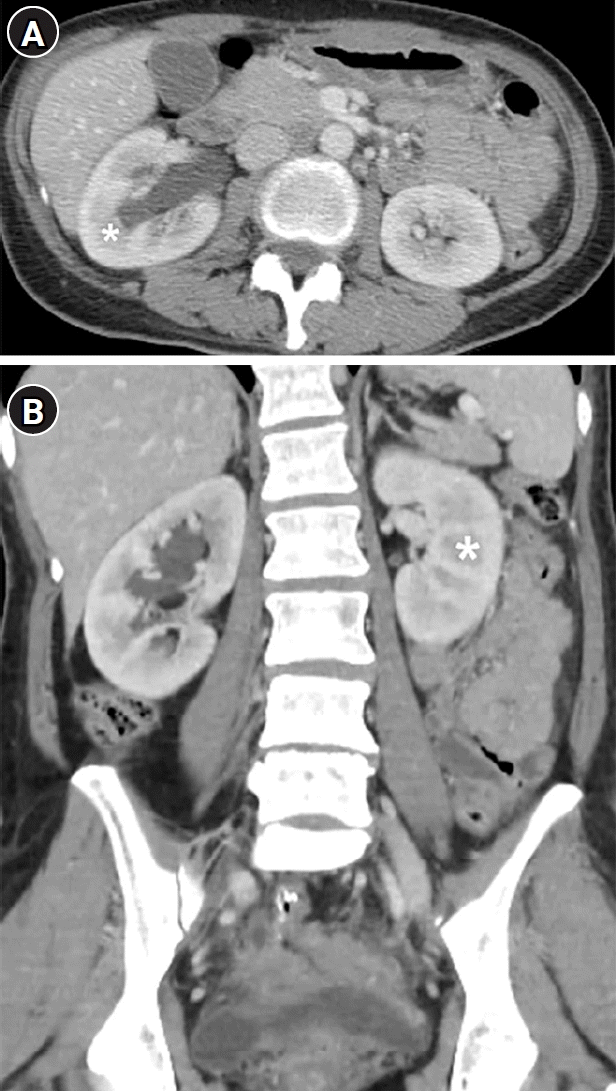

Fig. 1.

Axial (A) and coronal (B) contrast-enhanced abdominal computed tomography images during the 70-second delayed portal venous phase, scanned 3 months before referral to the nephrology department, show right hydronephrosis without delayed nephrogram in the right kidney. Both kidneys show brisk enhancement in the renal cortices and slight low attenuation remaining in the renal medullae (asterisks). Renal sizes are within the normal range. There is no evidence of urinary calculus or a mass obstructing the urinary tract; therefore, the right hydronephrosis was thought to be due to postoperative adhesion with no clinical significance.